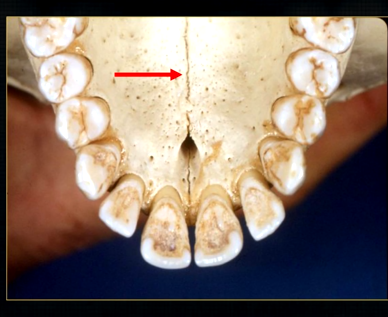

what is this thin line over the palate?

mid-palatal suture

what is this large hole?

naso-palatine foramen